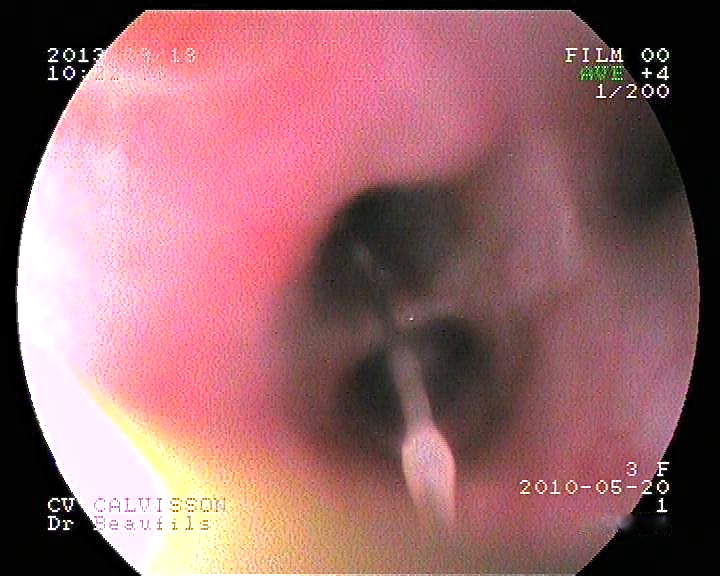

Extraction réussie chez une jeune épagneul qui toussait depuis trois mois, après avoir passé une heure à courir dans un champ de blé. Ci-dessus à gauche : une longue barbule émerge d’une bronche du lobe caudal du poumon droit. A droite : contrôle de la bronche après extraction de l’épillet. Il n’y a pas d’autre corps étranger visible, mais la muqueuse est très enflammée, et on note un important spasme de la bronche. Une autre extraction, celle-ci en live, est visible sur la vidéo ci-dessous.

Recherche et extraction, en live, d’un épillet bronchique chez Gina, jeune épagneul breton de trois ans. Cette chienne était référée à la clinique vétérinaire de Calvisson car elle toussait depuis un mois, malgré les traitements anti-tussifs classiques. L’exploration des différentes bronches a permis la mise en évidence, puis l’extraction, d’un bel épillet !